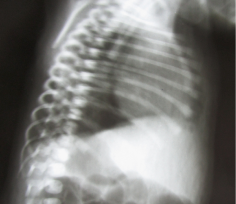

A one day male was admitted with frothing and respiratory distress and absent anal opening. The patient was a full term normal delivery with a birth weight of 2.2kg and cried immediately after birth. Antenatal history was not significant.2 On examination, the patient had an imperforate anus with poorly developed buttocks. A red rubber catheter could be passed orally only up to 8 cm from the alveolar margin. Radiographic studies confirmed the findings of EA with TEF (Figure 1). Cross table prone X ray was indicative of high ARM (Figure 2). Routine laboratories were within normal limits. TEF repair was done via right thoracotomy extrapleural approach. On laparotomy for colostomy, the colon was absent with the small bowel was completely developed up to the ileocaecal junction, and a blind ending caecum with appendix was present (Figure 3). There was no dilatation of the proximal ileum and there was no enterovesical fistula. End caecostomy was performed however the patient succumbed to sepsis on postoperative day 3.3-5

Figure 2 Cross table prone X ray was indicative of high ARM.